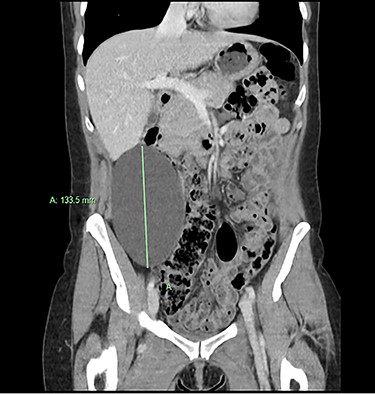

We present an extremely rare and isolated case of primary mixed serous and mucinous cystadenoma in a 49-year-old otherwise fit and healthy female patient. She was referred to our consultant with a history of discomfort on the right side of her abdomen for few years, which increased gradually with no other complains. The patient had further investigations conducted including computed tomography (CT) (Figs 1 and 2) that demonstrated the position and size of the lesion. The magnetic resonance imaging (MRI) revealed a large cystic lesion in the right retroperitoneal region shown in Figs 3 and 4. Her full blood count, inflammatory markers, urea and electrolytes and liver function tests were within the normal limit. Consequently, the patient had a laparoscopic resection of an isolated retroperitoneal cyst. At surgery, the cystic lesion seemed to be arising from mesentery and the lesion was dissected intact and completely excised. Histopathology revealed a benign mixed serous and mucinous cystadenoma as shown in Fig. 5. The patient was discharged from the hospital with no complications and fully recovered on follow-up review. Patient was discussed in a multidisciplinary team meeting and the recommendation was for no further management.

Serological investigations are not helping with providing a definitive diagnosis. Tumour markers such as, carbohydrate antigen (CA) 19–9, CA 15–3, CA 125, carcinoembryonic antigen (CEA), alpha feta protein have not been shown to be sensitive or specific. Some cases demonstrated an increase in CEA and CA 19–9 in associated with PRMC. However, these are isolated case studies. With regard to radiological investigation, the ultrasonography lacks specificity [11]. Radiological imaging, such as MRI and CT, plays an important role in describing and assessing the disease’s characteristics and the involvement of adjacent or distant structures of the mass. None of the modalities can exclude the malignant potential of the retroperitoneal masses [9], as the diagnostic value of CT and MRI is similar [12]. Predominantly male patients and the patients who present with solid nodules in the cyst on their radiology images have strong association with malignancy [13].